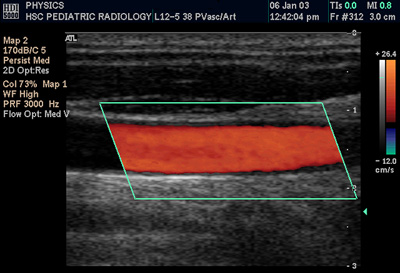

Una ventaja de la medición de este valor frente a otros métodos es que puede realizarse de una forma no invasiva. Puede hacerse de forma directa, a través del ultrasonido, o de forma indirecta, con resonancia magnética nuclear, o midiendo la velocidad de la onda de tránsito.

- Ultrasonido. La valoración por ultrasonido puede utilizarse para evaluar la distensibilidad arterial. Se prefiere la medición en arterias grandes como la aorta abdominal o la femoral. Para realizar la medición, el médico debe buscar la imagen donde se observe mejor la pared arterial y comenzar a grabar durante algunos minutos. El video se analiza para buscar el momento de mayor y menor expansión del vaso estudiado, y con esos valores se calcula la distensibilidad a partir de una fórmula matemática que incluye el valor de presión arterial. A pesar de que el ultrasonido tiene la ventaja de ser un método no invasivo, el resultado depende del médico que esté realizando el estudio. Es decir, la confiabilidad del valor final está condicionada a la experiencia del médico que lo haya realizado.